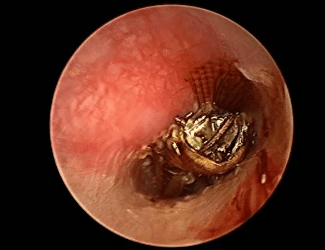

可怕!女子感觉耳朵里有异物,医生从里面取出了一只活蜘蛛

图片尺寸640x710